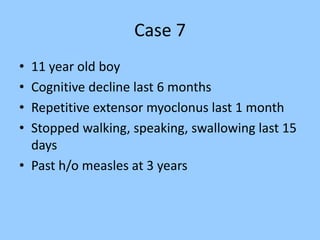

2. Case studies are presented with clinical histories and EEG findings to illustrate different pathologies. Treatment options are also mentioned for many of the conditions.

3. International standards for EEG electrode placement and recording parameters are reviewed. Characteristics of different EEG waves, amplitudes, and patterns are described.